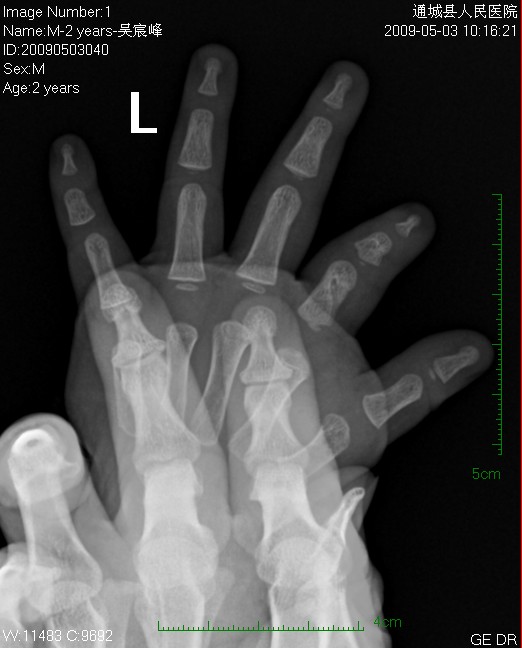

男  2岁  左手食指发育短小,指骨粗短,外表肤色、功能无异。

食指近节指骨中边缘光整的“缺损”会是粗大的营养血管沟吗?

左手食指发育异常;食指近节指骨中边缘光整的“缺损”,可能为粗大的营养血管沟。

左手食指发育不良,但楼主所述处应该是营养血管沟影。